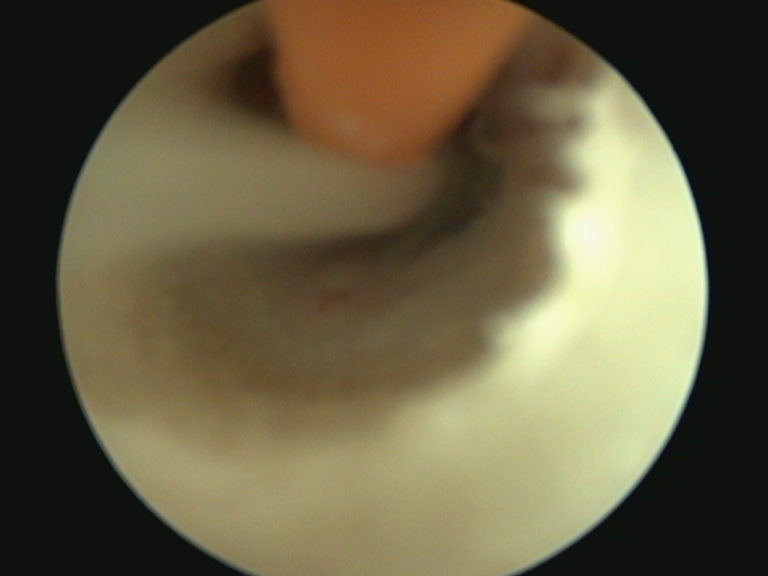

A 5mm red rubber tube is used to flush thick purulent material from the tympanic bulla using video-otoscopy

The patient was anesthetized for video-otoscopy and deep ear flush. Myringotomy of the left ear yielded copious amount of tan, thick mucopurulent fluid. A small amount of purulent material was also found in the right tympanic bulla. Both tympanic bullae were sampled for bacterial culture and sensitivity; they were subsequently flushed with sterile saline. After consultation with Internal Medicine, a swab for an Upper Respiratory Disease RealPCR Panel was also performed to evaluate for causes of nasal congestion. The patient awoke without complications, and was sent home on a course of oral marbofloxacin pending culture results.